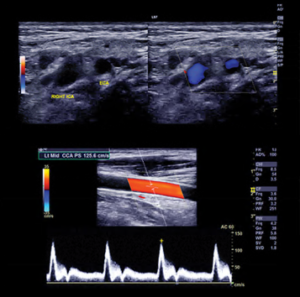

- Demonstrate clinical interpretation of arterial and venous vascular noninvasive studies in the peripheral, cerebrovascular and abdominal systems

- Discuss the clinical application of velocity criteria for grading of stenosis in the vasculature including dialysis grafts, endovascular interventions in the aorta and peripheral system, and bypass grafts

- Summarize basic ultrasound physics and ultrasound technology as it applies to vascular diagnostics